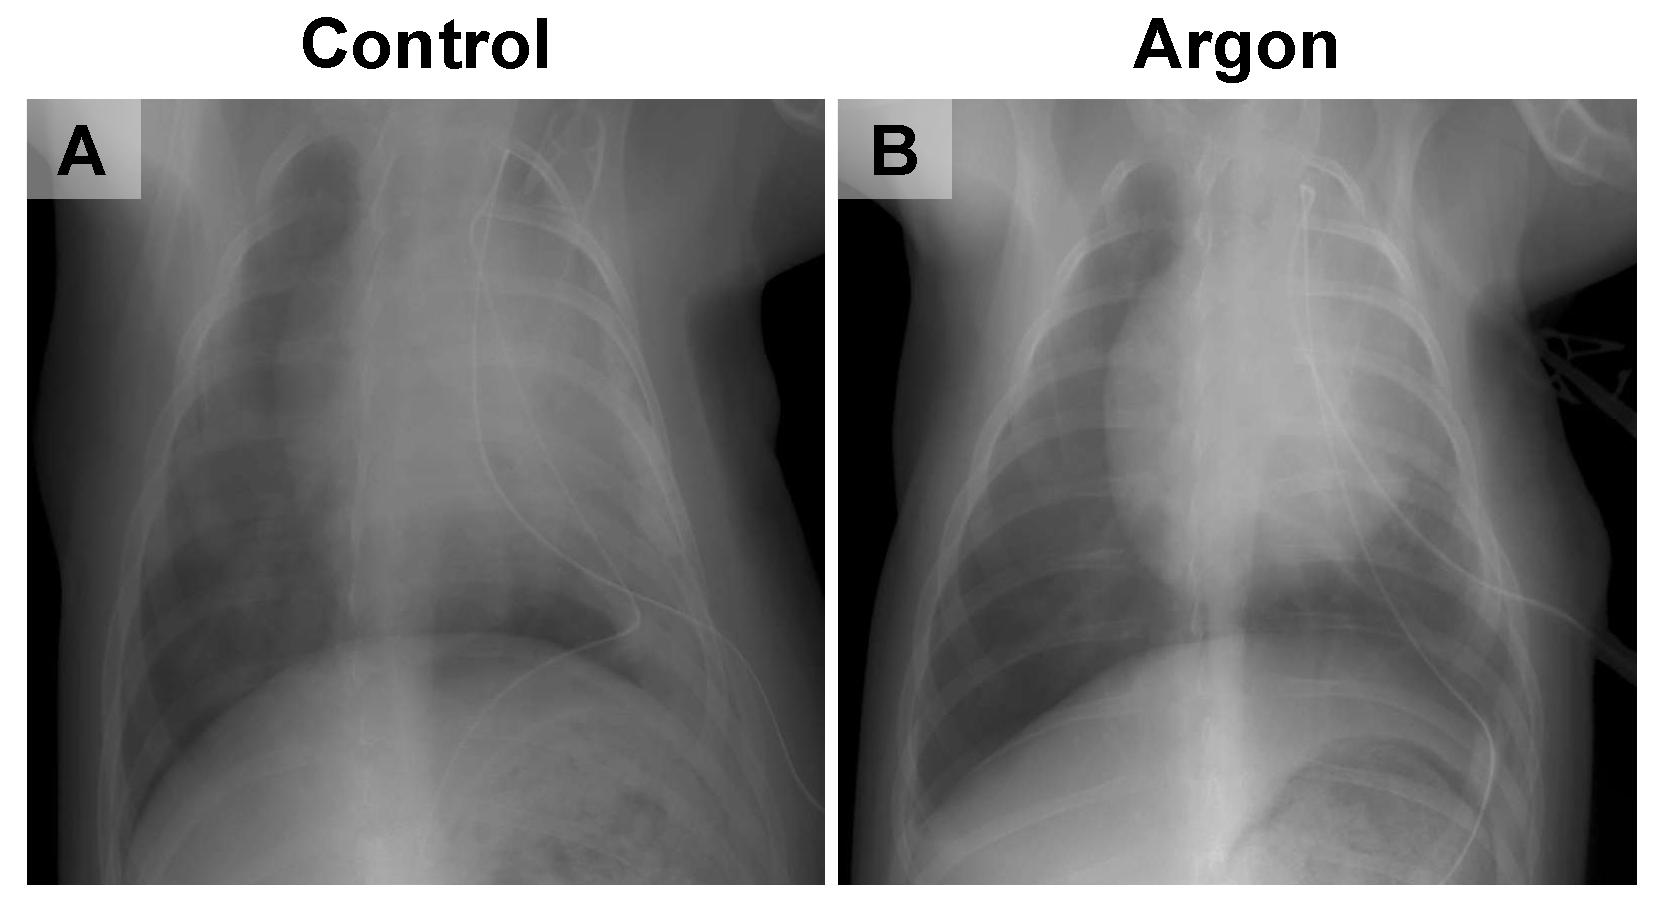

再灌注后2天的胸部X光片显示,对照组大鼠肺部出现明显浸润影,且肺扩张程度降低;而氩气处理组大鼠的肺扩张功能得以维持,仅见轻微肺部浸润影(图4)。再灌注后7天,两组大鼠均出现恢复迹象,且组间无明显差异;再灌注后14天和28天的影像学结果显示,两组大鼠的肺部均已完全恢复,因此未展示这两个时间点的影像图片。

图片4.png

4 对照组(A)与氩气(Ar)处理组(B)大鼠的代表性胸部X光片

对照组大鼠肺部出现明显浸润影,且肺扩张程度降低;而氩气处理组大鼠的肺扩张功能得以维持,仅见轻微肺部浸润影。